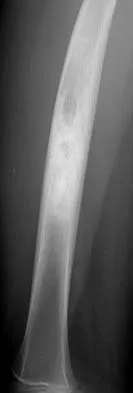

A 10-year-old boy with a history of retinoblastoma now reports right knee pain. AP and lateral radiographs are shown in Figures 3a and 3b. What is the most likely diagnosis?

The radiographs show a bone-producing lesion in the femoral diaphysis. The radiographic appearance of small round cell tumors is more permeative with an elevated periosteum and no matrix production. The appearance of this lesion is most consistent with osteosarcoma. Patients who carry the Rb gene are predisposed to osteosarcoma. However, Ewing's sarcoma, primitive neuroectodermal tumor, and osteomyelitis can all occur in this location. Unni KK: Dahlin's Bone Tumors: General Aspects and Data on 11,087 Cases, ed 5. Philadelphia, PA, Lippincott-Raven, 1996, pp 143-160.